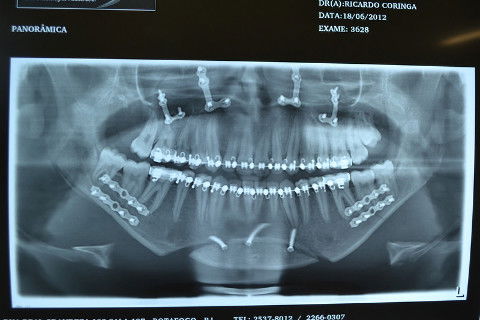

Radiografia Panorâmica pós operatória...